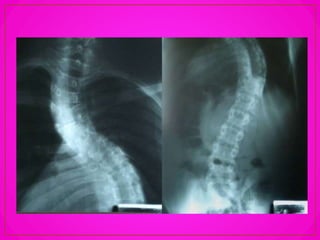

• La escoliosis o desviación

lateral de la columna, es la

más grave de las lesiones

debido a que los cuerpos

vertebrales giran uno sobre

otro y como la mayor parte de

las vértebras susceptibles de

rotación son dorsales y están

unidas a las costillas estas

también se desplazan hacia

adelante en un lado y hacia

atrás en el lado opuesto.